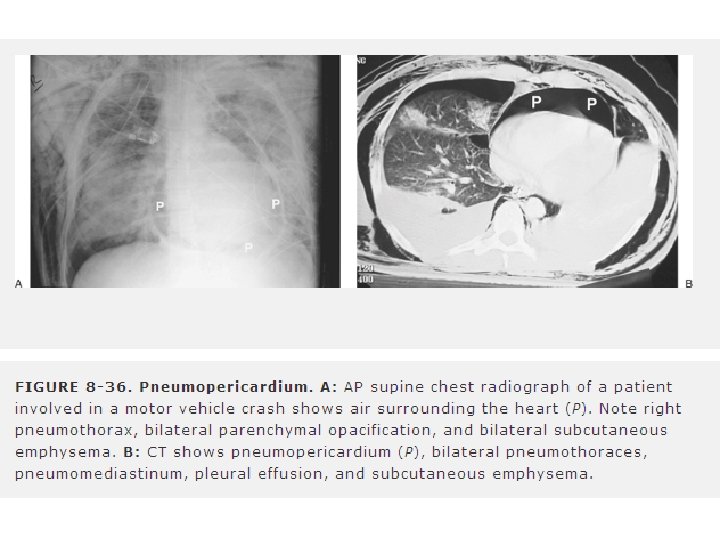

A. BASİT PNÖMOTORAKS • Visseral ve pariyetal plevra arasındaki potansiyel boşluğa havanın girmesi • Künt travma en sık nedenidir. • Etkilenen bölgede akciğer sesleri azalır. • Perküsyonda hiperrezonans • Ayakta + ekpirasyonda + PAAG • Anterior ve midaksiller hat arasında 4. veya 5. interkostal aralıktan takılan göğüs tüpü ile tedavi edilir. • Gözlemi ve/veya aspirasyonu risklidir. • Göğüs tüpü takılmadan asla genel anestezi veya pozitif basınçlı ventilasyon uygulanmamalıdır. • Hayatı tehdit edici tansiyon pnömotoraksa dönüşebilir

D. TRAKEABRONŞİAL AĞAÇ YARALANMALARI • Nadir ancak potansiyel olarak fataldir. (Mortalite yüksek) • Sıkça gözden kaçar. • Künt travmada, yaralanmaların büyük bölümü karinanın 1. 5 cm’lik mesafesi içinde meydana gelir. • Mortalite oranı yüksektir. • Trakeabronşial yaralanma şüphesi acil cerrahi konsültasyon gerektirir. • Hemoptizi, subkutan amfizem veya mediastinal şiftle birlikte TP varsa şüphelenilmelidir. • Tüp torakostomi sonrası fazla miktarda hava kaçağı devam eden pnömotorakslı hastalarda trakeabronşial yaralanmadan şüphelenilmelidir.

• Mediastinal amfizemi varsa özefagial ve trakeabronşial yaralanma? • Mediastinal hematom yada plevral kep büyük damar yaralanması • Nonoperatif değerlendirme planlanıyorsa acil anjiografi veya helikal CT • Anjiogram negatifse suda çözünür kontrast özefagografi • Trakeabronşial ağacın değerlendirilmesi için bronkoskopi • Kalp ve perikard USG ve BT • Mortalite hızı %20